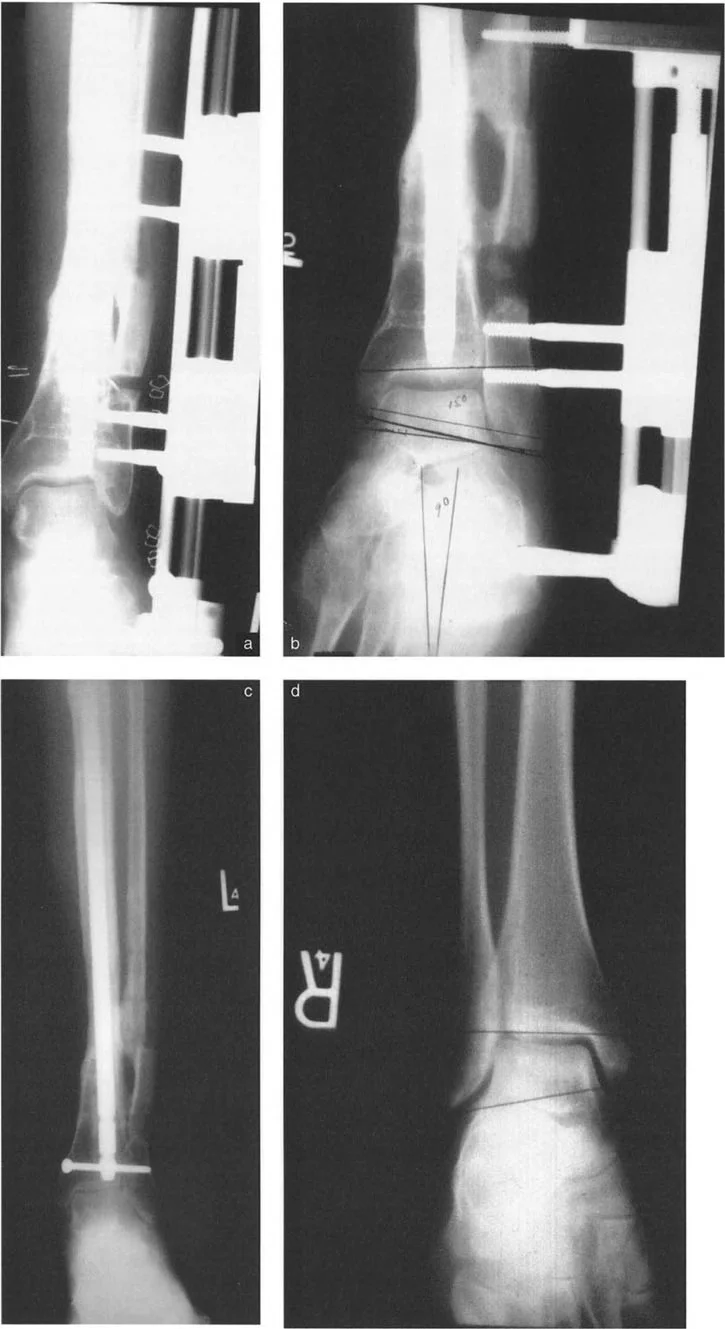

أنواع جراحات قطع العظم فوق الكاحل (Supramalleolar Osteotomy)

جراحة قطع العظم فوق الكاحل (SMO) هي الإجراء الأكثر شيوعًا لتصحيح تشوهات قصبة الساق البعيدة. تتضمن هذه الجراحة قطعًا دقيقًا في عظم الساق (القصبة) فوق مفصل الكاحل مباشرة، ثم إعادة محاذاة العظم وتثبيته في الوضع الصحيح. هناك عدة أنواع من هذه الجراحة:

1. قطع العظم الإسفيني الفاتح (Opening Wedge Osteotomy):

• يتم عمل قطع في العظم ثم فتح فجوة صغيرة فيه. تُملأ هذه الفجوة عادةً بترقيع عظمي (من جسم المريض أو من متبرع).

• المميزات: يحافظ على طول الطرف، وهو مفيد إذا كان المريض يعاني أيضًا من اختلاف في طول الساقين.

• العيوب: يتطلب ترقيعًا عظميًا، ويستغرق وقتًا أطول للالتئام، وقد يزيد من توتر الأنسجة الرخوة حول العظم.

3. قطع العظم القوسي البؤري (Focal Dome Osteotomy):

• يتم عمل قطع منحني في العظم، مما يسمح بتصحيح